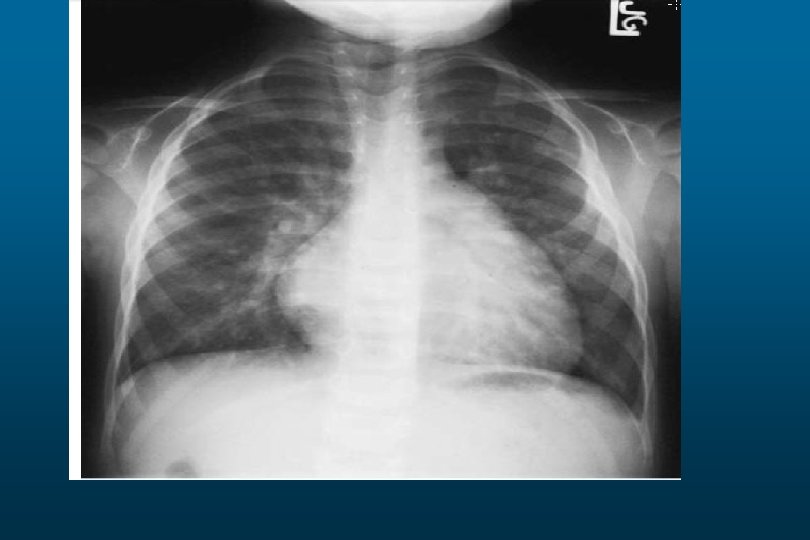

Tuberculosis